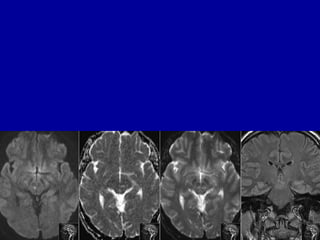

Cisternal segment of oculomotor nerve

BA Cn 3SCA

PCA

Cisternal segment

ICA